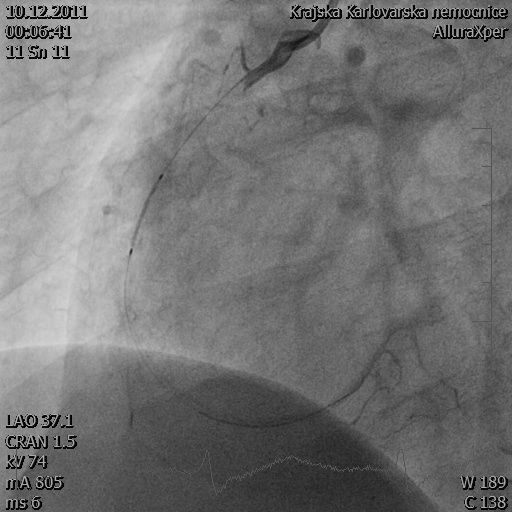

Příchod pracovníků anesteziologicko-resuscitačního oddělení, nalezena cyanóza, neměřitelná saturace, podán Midazolam 5 mg, endotracheální intubace rourkou číslo 8,0, UPV (umělá plicní ventilace) pomocí režimu SIMV (Synchronized Intermittent Mandatory Ventilation – plně řízený ventilační režim), zaveden permanentní močový katetr s teplotním čidlem a podán studený FR o objemu 1 000 ml do periferního žilního katetru. Pacient je odvezen na kardiointervence, kde probíhá 60minutový výkon s nálezem stenózy jednoho segmentu, aplikován jeden stent.

Snímek pořízený při katetrizaci

Zdroj: Fotoarchiv kardiologického oddělení nemocnice Karlovy Vary, 2011